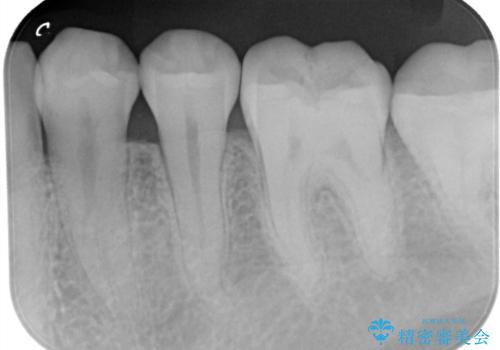

レントゲンなどから隣接面にも、う蝕があることが判明しました。